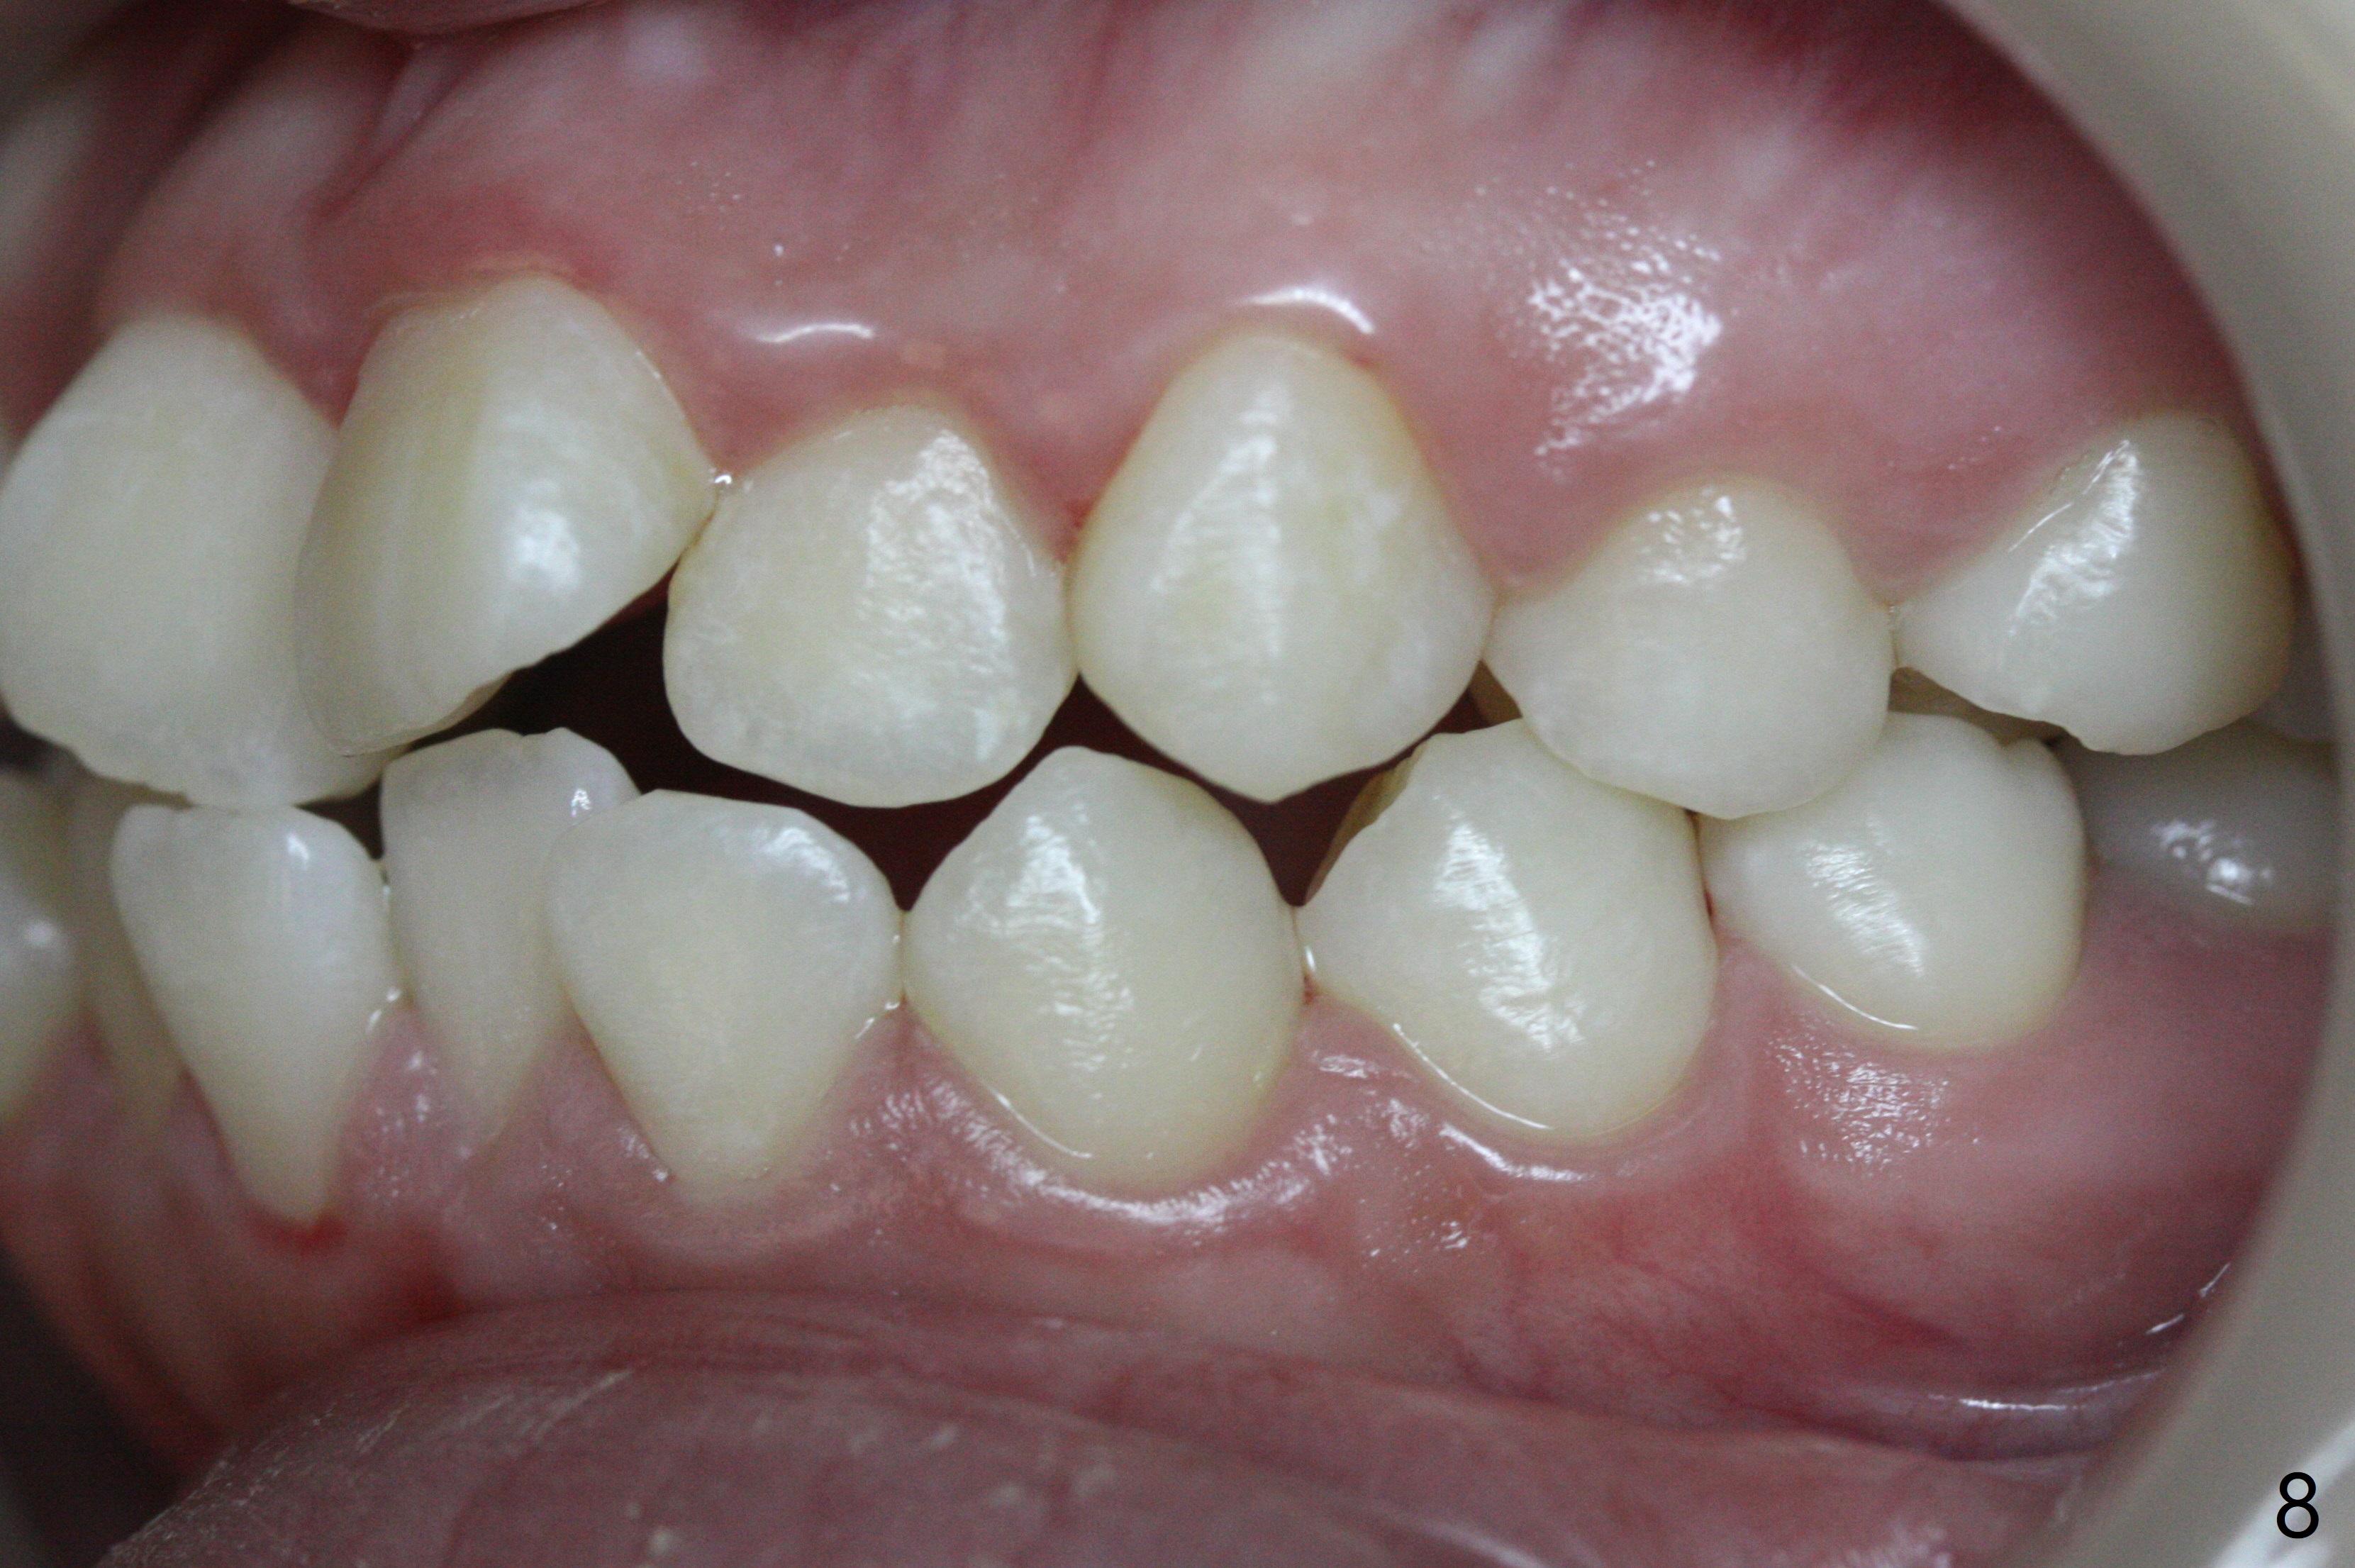

A 14-year-old woman has convex facial profile (Fig.1-4) with the upper midline shifted to the left (Fig.2). Since the roots of the 1st bicuspids are short (Fig.5), extraction should be easy. U3 will be retracted distal early with intention to correct the upper midline. With Class I occlusion at the canines and the 1st molars and good initial interdigitation (Fig.6-11), orthodontic treatment should be rewarding. Because of severe crowding (tight contact, Fig.12,13), place separators after extraction and place bands and brackets a few days later. Cephalometric analysis (Fig.14) shows that SNB is greater than SNA (82.4 vs. 81.8 degree); after extraction, retract the lower anterior teeth prior to the upper ones. It is easy to place separators after extraction (Fig.16,17).